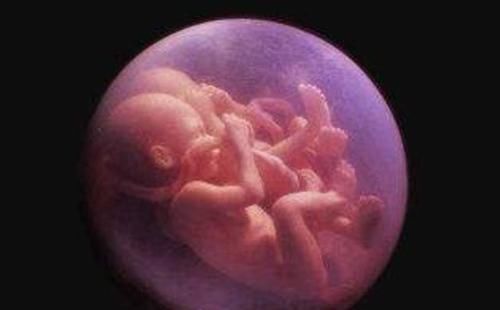

【 宝妈|孩子出生自带“金钟罩”,护士连连道喜,产妇:我生了个哪吒?】终于到了分娩这天,丈夫主动提出要陪产,因为是初产妇,小青生娃的时间比较长。过去了大半天的时间,小青终于在医护人员的指导下,顺利生下了一个可爱的宝宝,但没想到孩子出生后却自带金钟罩。因为小宝宝刚出生的时候,外面包裹着一层透明的壳,看上去就像一层保护罩。

对此产妇很是不解:难道我生了个哪吒,而小青的丈夫也被小婴儿的模样吓坏了,特别着急,以为孩子是身体方面有疾病,一时之间没有忍住悲伤的情绪,眼泪直接掉了下来。而护士看到宝宝的模样之后却连连道喜,护士告诉家人,小宝宝的这种情况很正常,说明身体非常健康,没必要担心。

而这层保护罩其实就是羊膜,它可以起到保护小婴儿的作用。